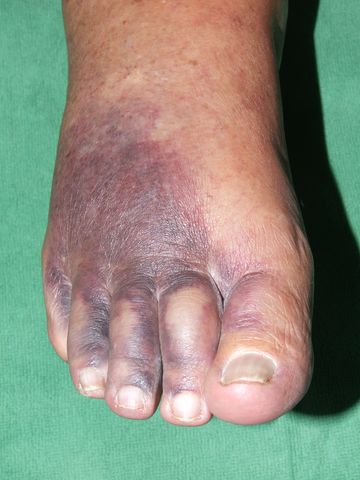

Cianosis acra. Isquemia.